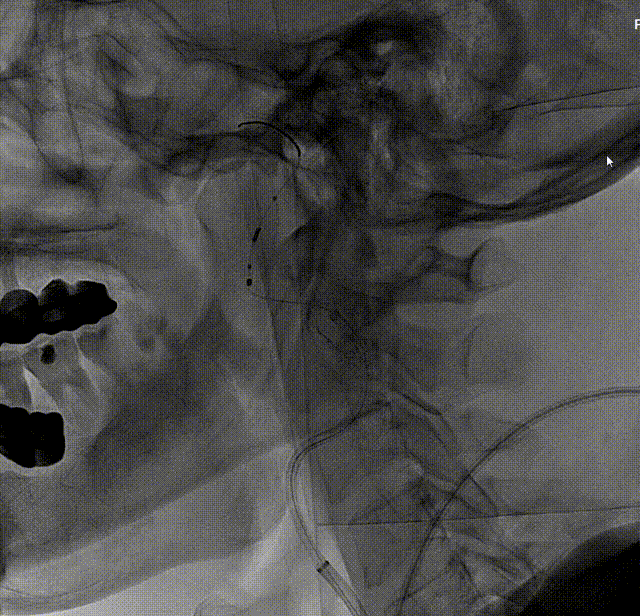

考虑到靶血管较迂曲,拟使用中间导管进行支架释放。在Workhorse导丝引导下,将中间导管通过迂曲段,经由中间导管送入8mm*40mm颈动脉支架至右侧颈内动脉狭窄处。回撤中间导管至颈总动脉后,在透视状态下准确释放支架。

造影显示残余狭窄小于30%,未进行后扩张。术后造影显示狭窄解除,支架置入部位满意,血流较术前明显改善。使用中间导管将Nav6保护伞顺利回收后,对股动脉穿刺点进行止血,患者安返病房。

Nav6由于其出色的安全性和独特的独立导丝技术,已成为CAS手术中术者常规应用的保护伞。在本病例中,由于患者颈内动脉起始处严重狭窄合并S形弯的解剖形态,使得保护伞和支架顺利到位变得挑战。在此类病变中,巧用6F中间导管并借助Nav6输送导管的有效支撑采用特洛伊木马及望远镜技术,可将保护伞顺利输送到C1远端平直处,为后续顺利治疗提供基础。